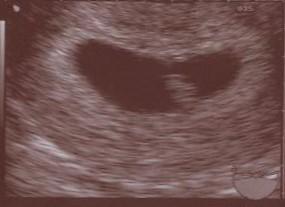

komme gerade vom Doc. Hab mal wieder ewig im Wartezimmer gesessen. Aber es hat sich gelohnt :) Babyleingeht es prima und es ist ordentlich gewachsen auf ca. 8 mm. Herzchen hat fleißig gebubbert. Hab meinen Mupa, Blut und Pippi abgegeben. ET wurde noch nicht bestimmt, das machen wir bei meinem nächsten Termin am 8.12. Aber er sollte in etwas mit meiner Berechnung hinkommen. Hoffe dann ist wieder alles in Ordnung. Hier noch ein Bildchen

Bild zu Zurücke von VU - Forum für Juli - Mamis